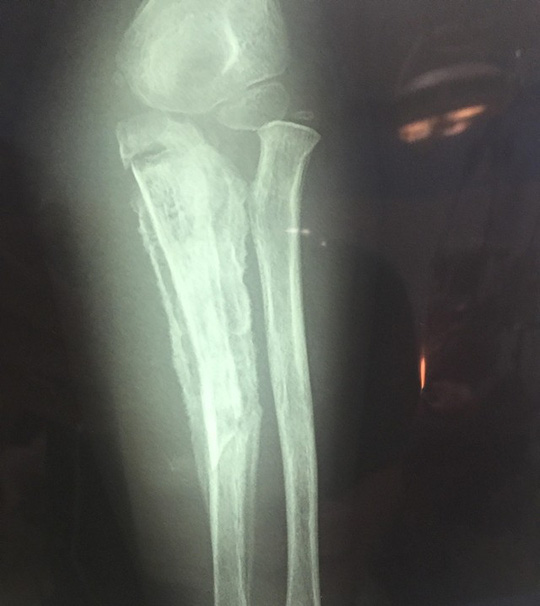

Bác sĩ Lê Tuấn Anh, Phó trưởng Khoa Chỉnh hình nhi, Bệnh viện Nhi Trung ương, cho biết khi được đưa đến bệnh viện, cẳng tay cháu M. có rò mủ, toàn bộ vùng cẳng tay trái sưng nề. Trên phim chụp X-quang thấy có hình ảnh viêm xương trụ, có 1 đoạn xương ở vị trí 1/3 giữa trên đã hoại tử, vùng khuỷu tay hạn chế gấp duỗi, các ngón tay co gấp, không duỗi được. Trong quá trình phẫu thuật, các bác sĩ đã tiến hành lấy bỏ ổ mủ, lấy bỏ đoạn xương trụ hoại tử dài 6 cm ở 1/3 giữa trên cẳng tay, bơm rửa ổ viêm xương, đồng thời đặt dẫn lưu và bất động cẳng tay bằng nẹp bột. Sau phẫu thuật, cháu M. được chỉ định dùng kháng sinh liều cao theo kháng sinh đồ. Hiện tại, bé M. đang được điều trị tại Khoa Chỉnh hình nhi.

Phim chụp X-quang cẳng tay cháu M. cho thấy cẳng tay bị gãy